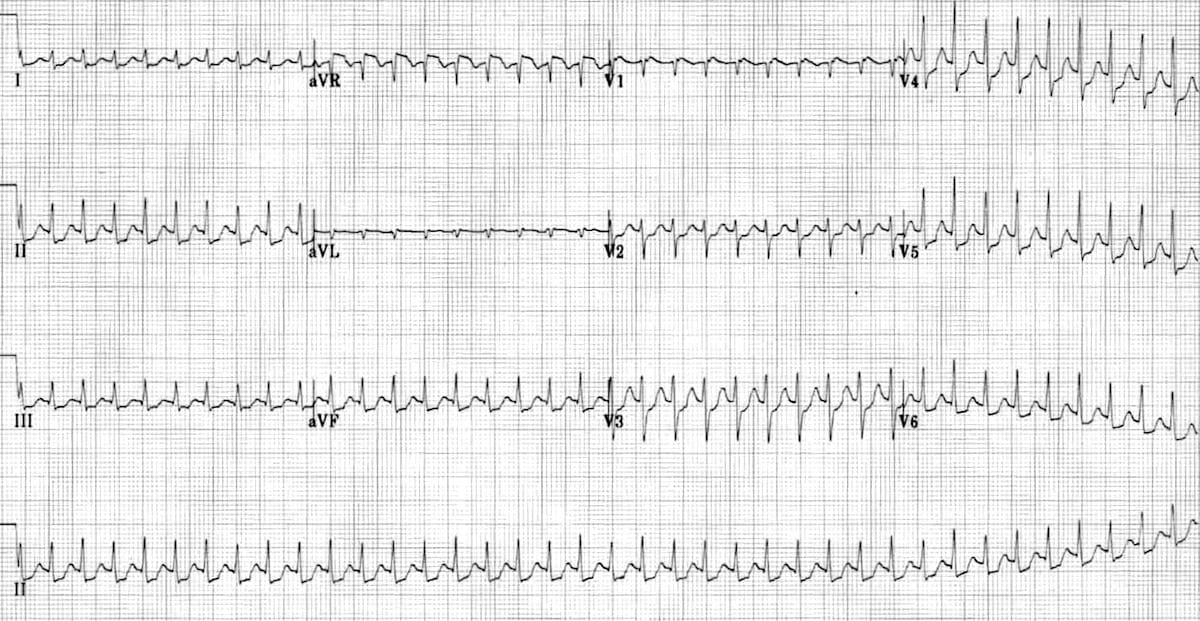

This ECG shows left axis deviation. Applying the thumb rule: lead I is up (+ve) and lead aVF is down (-ve). The left axis deviation is secondary to left ventricular hypertrophy.

© Life in the Fast Lane. Licensed under CC BY-NC 4.0

This ECG shows right axis deviation. Applying the thumb rule: lead I is down (-ve) and lead aVF is up (+ve). The right axis deviation is secondary to right ventricular hypertrophy (from cor pulmonale).

https://litfl.com/top-100-ecg-cases/

© Life in the Fast Lane. Licensed under CC BY-NC 4.0